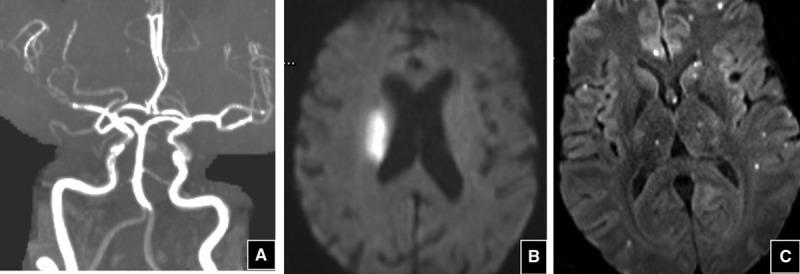

The severe acute respiratory syndrome coronavirus 2 or coronavirus disease 2019 (COVID-19) pandemic has raised concerns about the correlation with this viral illness and increased risk of stroke. Although it is too early in the pandemic to know the strength of the association between COVID-19 and stroke, it is an opportune time to review the relationship between acute viral illnesses and stroke. Here, we summarize pathophysiological principles and available literature to guide understanding of how viruses may contribute to ischemic stroke. After a review of inflammatory mechanisms, we summarize relevant pathophysiological principles of vasculopathy, hypercoagulability, and hemodynamic instability. We will end by discussing mechanisms by which several well-known viruses may cause stroke in an effort to inform our understanding of the relationship between COVID-19 and stroke.

严重急性呼吸综合征冠状病毒2型或冠状病毒病2019(COVID-19)大流行引发了人们对这种病毒性疾病与中风风险增加之间相关性的担忧。尽管在大流行初期了解COVID-19与中风之间关联的强度还为时过早,但现在是回顾急性病毒性疾病与中风之间关系的恰当时机。在此,我们总结病理生理原理和现有文献,以指导理解病毒可能如何导致缺血性中风。在回顾炎症机制后,我们总结血管病变、高凝状态和血流动力学不稳定的相关病理生理原理。我们将通过讨论几种知名病毒可能导致中风的机制来结束本文,以便增进我们对COVID-19与中风之间关系的理解。